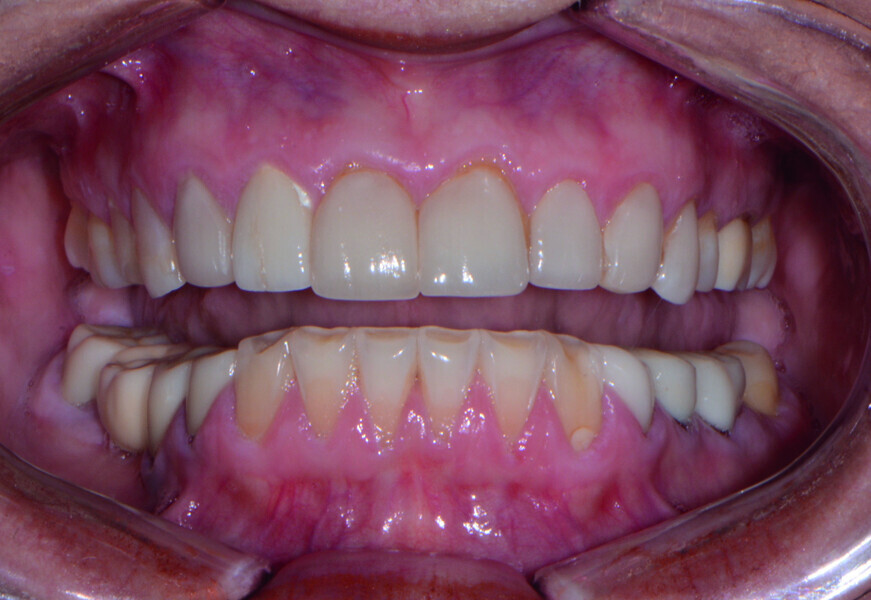

Restoring function and aesthetics with monolithic zirconia restorations